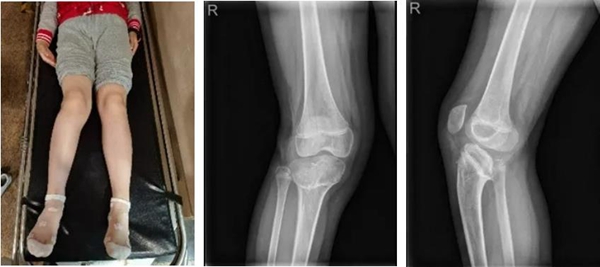

“医生伯伯,我老是被同学说腿怪怪的。”在广州第一人民医院9岁小李妹妹对医生这样说道。据患者家属描述,2016年9月小李妹妹因夹伤所致右下肢膝关节骨折,彼时当地医院对其进行了固定手术。但术后却逐步出现右下肢畸形,且越来越严重以致步态异常。

△小李妹妹的腿部状况;X线片

在丁焕文教授的安排下小李妹妹进行X线片、CT、MR等传统影像检查,患儿X线片和CT扫描二维断面图像均发现患者右膝有严重后倾畸形改变。于是,拿到CT数据的树蚁智能数字精准外科云服务系统团队使用建模软件对患者的全下肢进行了精准分离式三维重建,对小李妹妹重建后的患处进行了解剖方位对齐和多方位的精准三维测量,发现小李妹妹因为骨骺外伤和多年肢体畸形原因,右下肢短缩明显,达41mm。

△临床诊断:右膝部畸形

1. 矢状面畸形:胫骨平台后倾26.4736°

2. 额状面畸形:内翻6°

3. 右下肢短缩畸形(41mm)